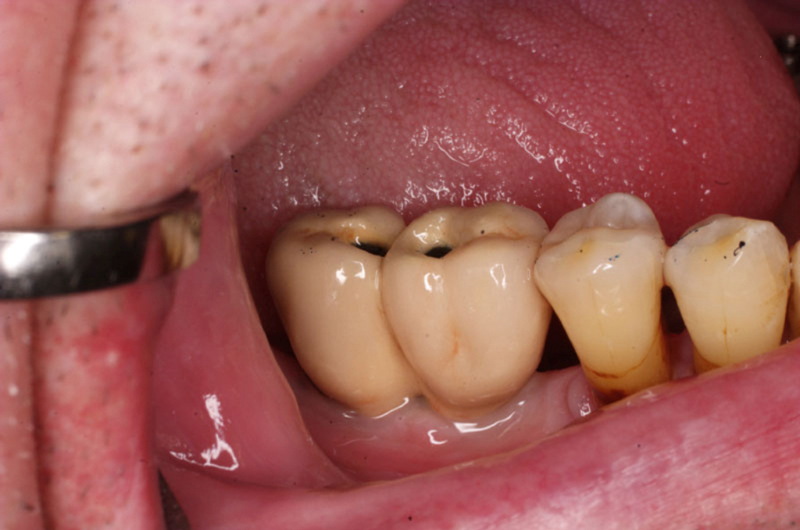

Velká mezera

V případě chybění většího počtu zubů v postranních úsecích čelistí je možné ošetření pomocí implantátů, které nahradí ošetření pomocí snímacích náhrad kotvených na zbývajících zubech nebo patře.

Podmínkou je opět dostatečné množství kosti.

Protetické řešení může být pomocí můstku, který je kotvený na implantátech nebo pomocí jednotlivých korunek na implantátech.

V zásadě je možné do těchto můstků zařadit i přirozené zuby, zejména pokud je potřeba tyto zuby ošetřit proteticky - korunkami. Korunky nebo můstky mohou být na implantáty nacementovány nebo přišroubovány.

Zdravé zuby zůstanou zachovány a přitom náhrady jsou pevné, jako na vlastních zubech